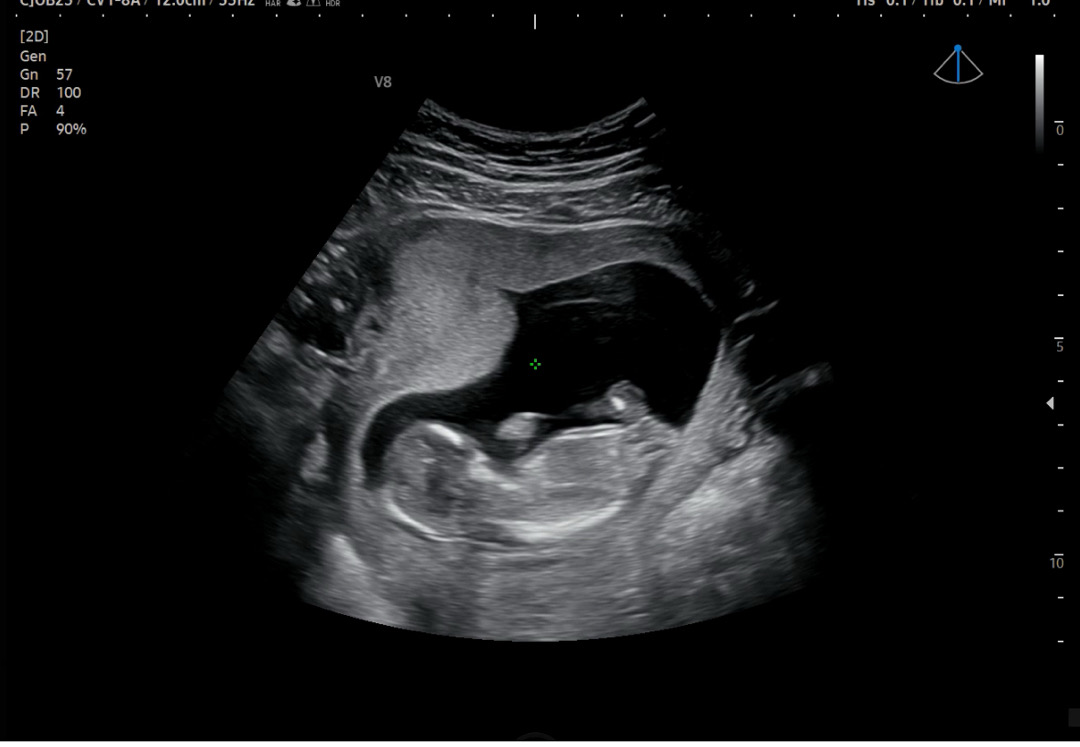

저번에 올렸는데 잘 안보인다구 하셔서 다시 올려봐여 12주 4일입니당